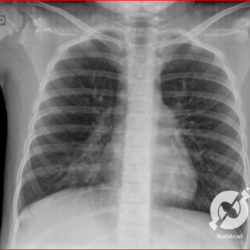

E o nome dado a esta alteração radiográfica que corresponde à substituição do ar alveolar por líquido é a consolidação alveolar.

Uma consolidação alveolar é, por definição, uma opacidade (imagem densa, branquinha) homogênea ou às vezes heterogênea (pela presença de calcificações ou cavidades), de limites mal definidos, exceto quando toca a pleura da parede ou das cissuras pulmonares. É um termo usado tanto em radiografia, como em tomografia computadorizada. Na tomografia, um outro termo é usado: vidro fosco, que é uma opacidade (branquinha mas não tanto como a consolidação), que borra o pulmão mas deixa ver os vasos de permeio (igual bigode de adolescente: dá pra ver todo o fundo).

Nós vamos mostrar aqui um pequeno apanhado de pneumonias de variados agentes, em diversos segmentos e lobos pulmonares, com extensões variadas. O objetivo é identificar o padrão radiológico de consolidação alveolar e não determinar o agente infeccioso, isso vai ser assunto para mais adiante. Aliás já antecipo que é fundamental saber localizar a lesão, porque alguns destes bichos gostam de determinados segmentos, alguns tumores também têm as suas preferências, então localização é fundamental. Se localização não fosse importante, um apartamento na beira do mar sairia o mesmo preço de um apartamento de frente pra BR-101, concordam?

Seguem alguns dos nossos casos de pneumonia para vocês treinarem os olhos e não se apavorarem nos plantões.